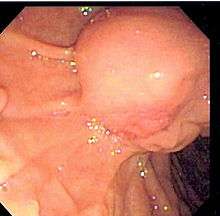

Common bile duct stone

Common bile duct stone, also known as choledocholithiasis, is the presence of gallstones in the common bile duct (thus choledocho- + lithiasis). This condition causes jaundice and liver cell damage, and requires treatment by cholecystectomy and/or ERCP.